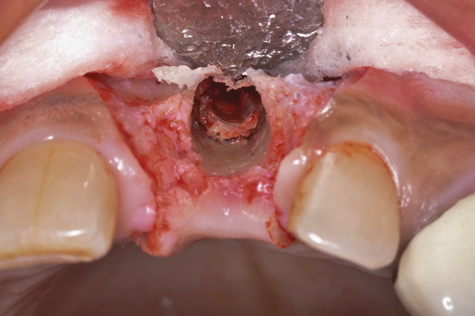

(6.) A 3.6-mm diameter implant was removed with a 4.0-mm diameter trephine drill. The apical portion of the implant was luxated carefully to preserve as much bone as possible.

Figure 6

(7.) Because apical and lateral bone volume was preserved with use of an ultrathin trephine, a wider diameter, 4.2-mm implant was placed at the time of implant removal. Bone augmentation was performed, and submerged healing was selected.

Figure 7